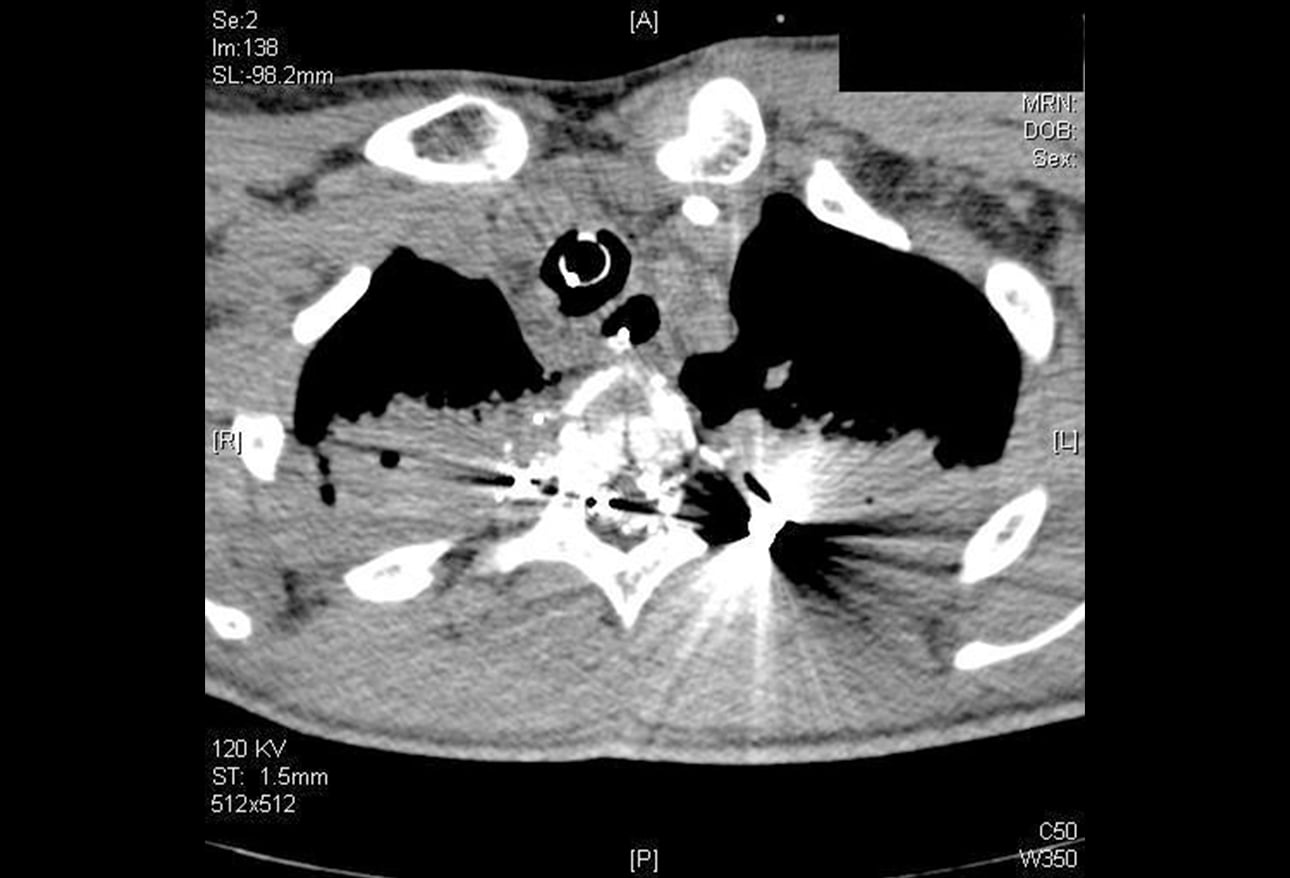

Firearm Injuries